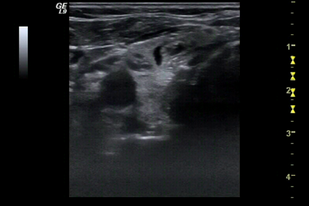

• Обложка: 1.5 Поперечная техника тонкоигольной аспирационной биопсии под контролем ультразвукового исследования